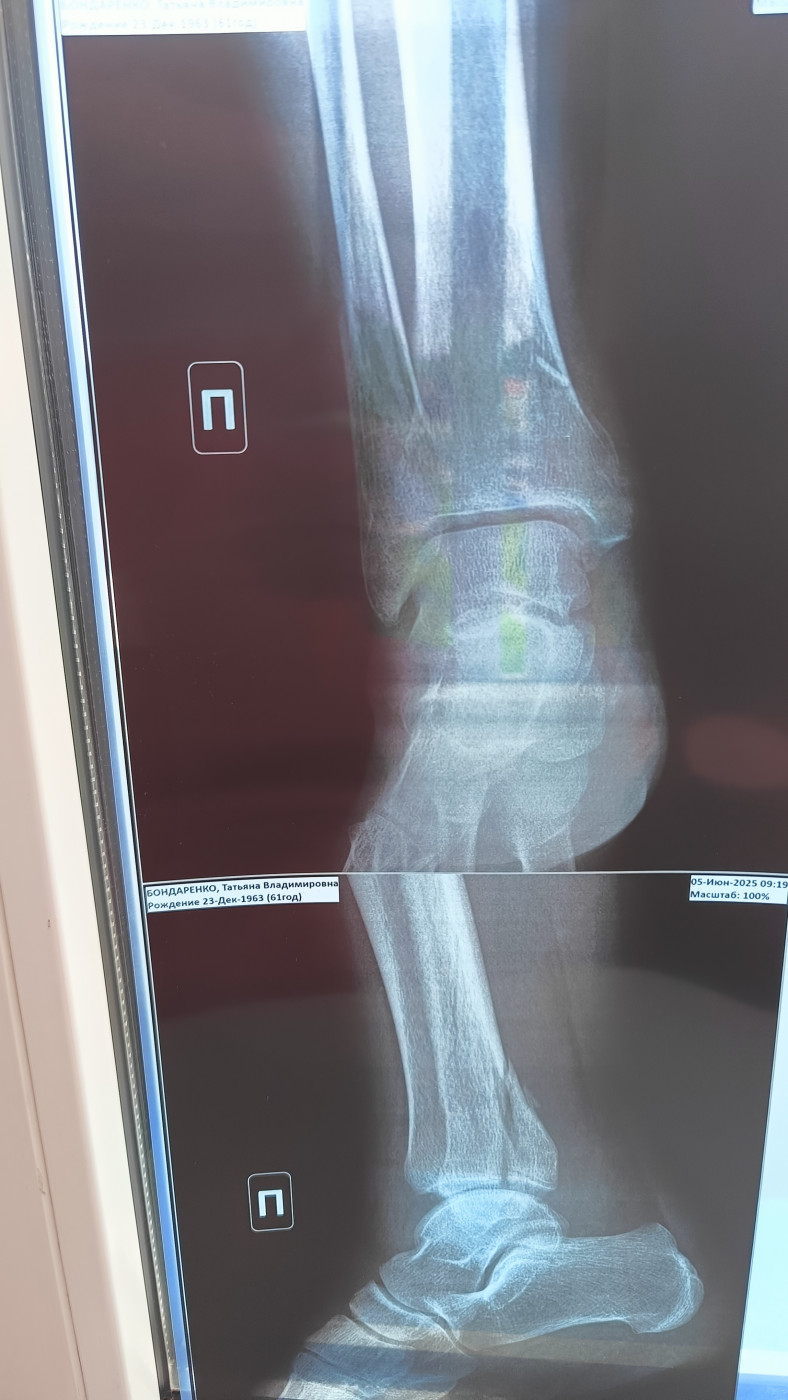

Целесообразность операции   2 ответа

Перелом правой лодыжки со смещением месяц назад, мнения врачей о необходимости операции разделились. Что посоветуете?